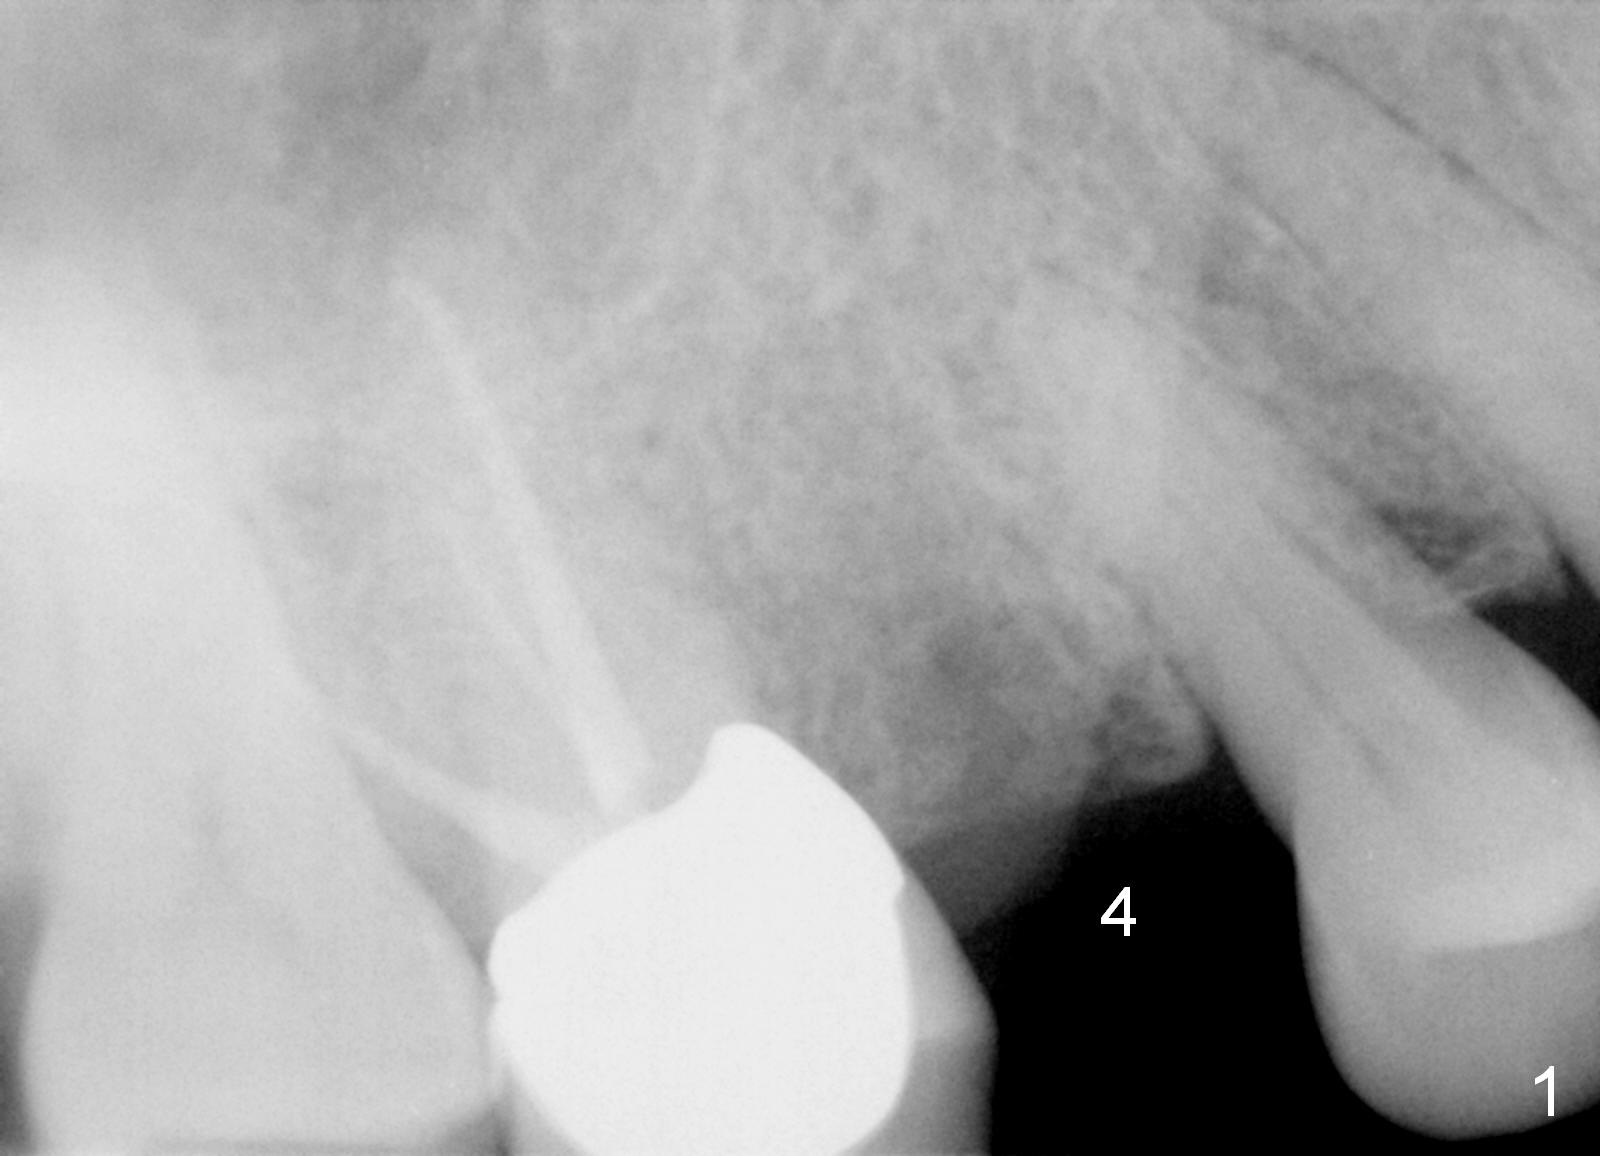

A 55-year-old lady had the tooth #4 extracted with socket preservation 4-5 months ago. The ridge does not look too narrow. Use a 3 mm tissue punch from the DIO 1 piece implant kit for access. Also prepare #15 blade. Since bone density within the healing socket seems low (Fig.1), use bone expanders, until 2-3 sizes smaller than the designed implant (4.5x14 mm, Fig.2). Pilot drill at 10 mm and take PA. After using the last bone expander, taken another PA. What is the real reason using bone expanders in this case, since the ridge is not so narrow?